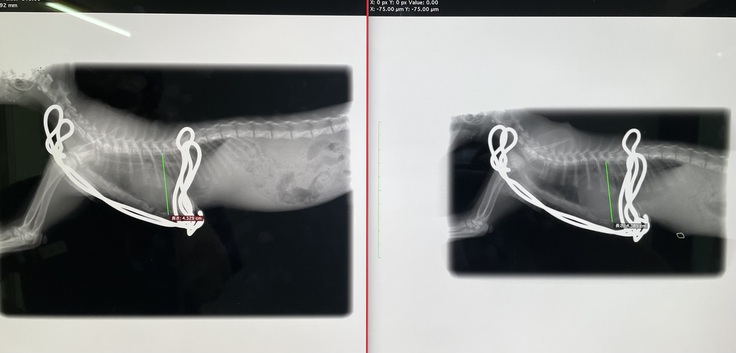

7/29(土)術後4回目の診察

術後はじめてのレントゲンを撮りました。

骨も戻ることなく、経過は順調です。

【本日撮影のレントゲン写真】

(左)本日 (右)7/9手術直後撮影

次回は8/5(土)の予定です。